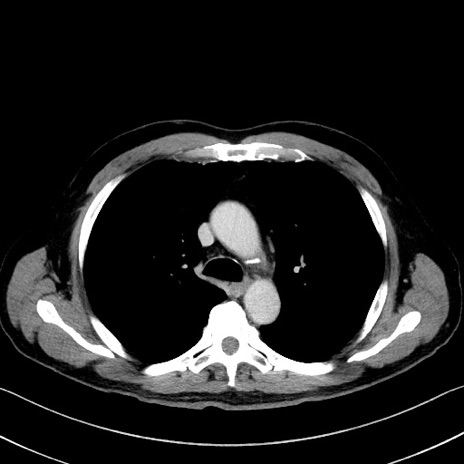

症例35(横断像)

【症例】70歳代 男性

【主訴】腹部膨満、嘔吐

【現病歴】昨日より腹部膨満感出現。本日増悪し、仙痛出現。嘔吐あり、受診。

【既往歴】糖尿病、胆摘後

【身体所見】BP 149/80mmHg、HR 74/min、BT 35.9℃、腹部:膨満、軟、圧痛なし。腸雑音減弱あり。上腹部正中切開瘢痕あり。

【データ】WBC 13500、CRP 1.72